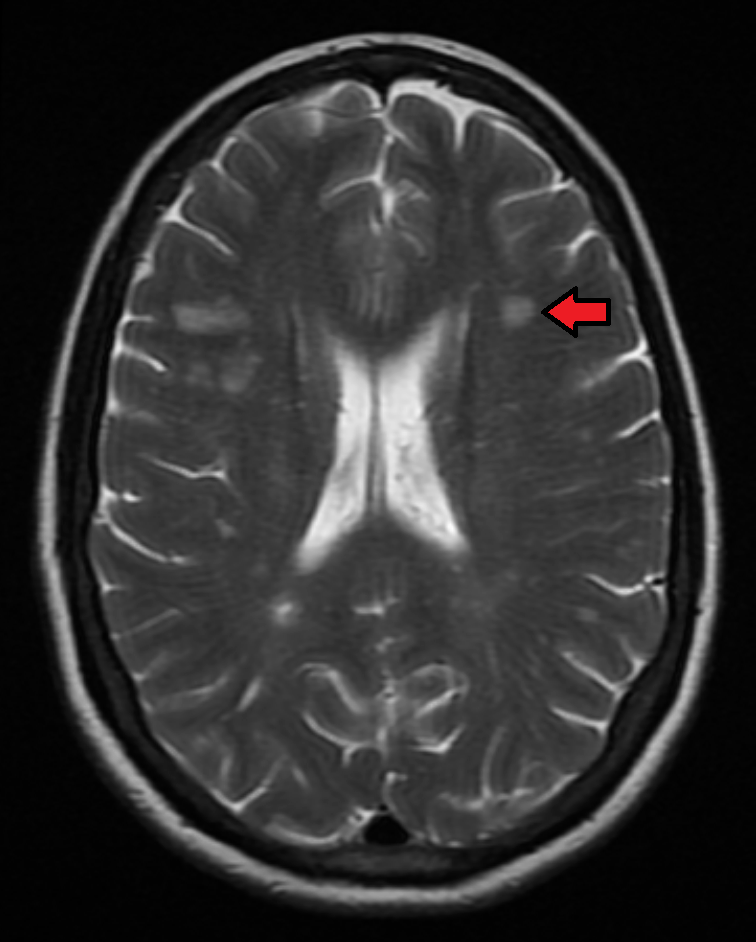

Демиелинизирующие заболевания мозга: МРТ изображения